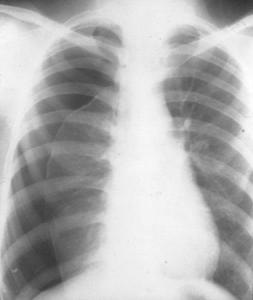

气胸是指无外伤或人为因素情况下,脏层胸膜破裂,气体进入胸膜腔导致胸腔积气而引起的病理生理状况。肺无明显病变由胸膜下气肿泡破裂形成者称特发性气胸;继发于慢阻肺肺结核等胸膜及肺疾病者称继发性气胸。按病理生理变化又分为闭合性(单纯性) 、开放性(交通性)和张力性(高压性)三类。[1]